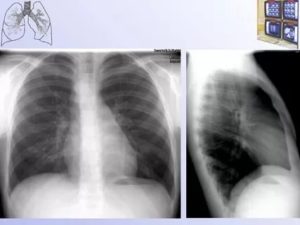

Пневмонияпневмония, боковая проекция

На представленной рентгенограмме органов грудной полости (прямая и правая боковая проекция) визуализируется округлое интенсивное образование нижней доли правого легкого. На боковом снимке отмечается инфильтрат области S8-9. Корни тяжисты за счет сосудов. Правый реберно-диафрагмальный синус завуалирован. Сердечная тень расширена влево.

При обследовании: выслушиваются хрипы в нижней доле правого легкого. Лицо гиперемировано, дыхание учащено, поверхностное.